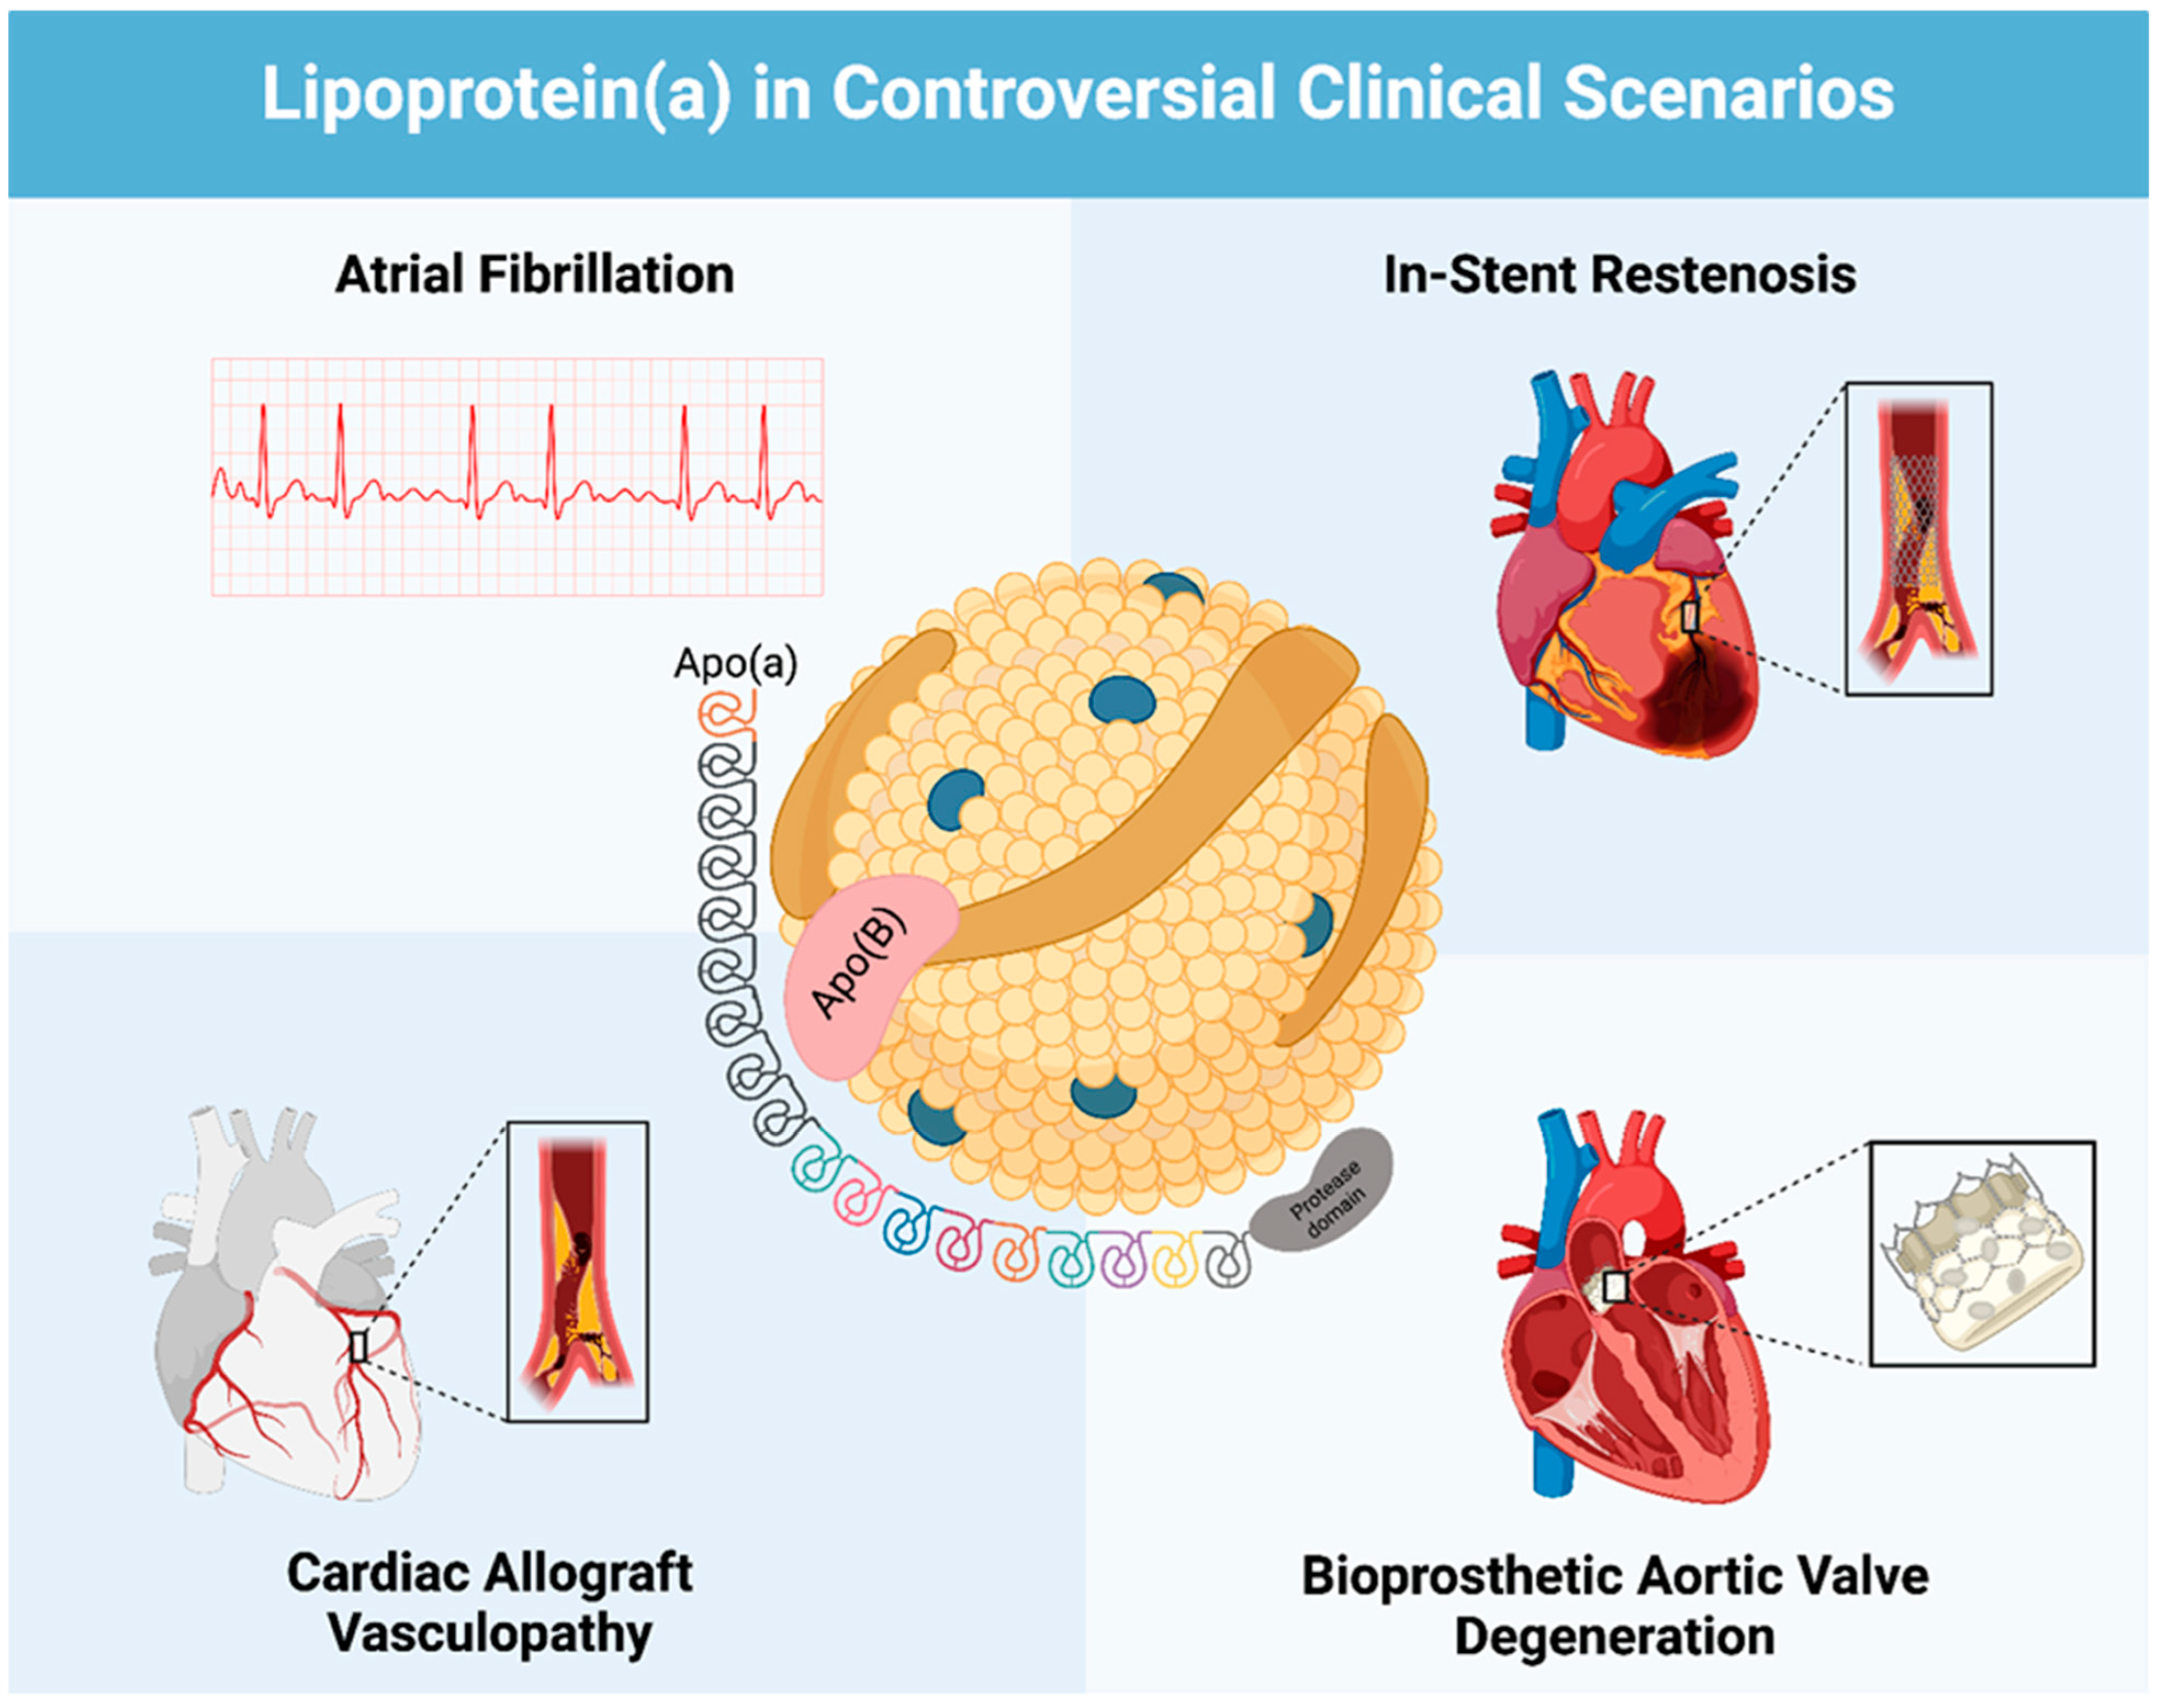

Lipoprotein (a) as a Cardiovascular Risk Factor in Controversial Clinical Scenarios: A Narrative Review

2.1. Lp(a) and Atrial Fibrillation

2.2. Lp(a) and In-Stent Restenosis

2.3. Lp(a) and Cardiac Allograft Vasculopathy

2.4. Lp(a) and Bioprosthetic Aortic Valve Degeneration

3. Discussion

3.3. Lp(a) and Atrial Fibrillation

3.4. Lp(a) and In-Stent Restenosis

3.5. Lp(a) and Cardiac Allograft Vasculopathy

3.6. Lp(a) and Bioprosthetic Aortic Valve Degeneration

5. Conclusions